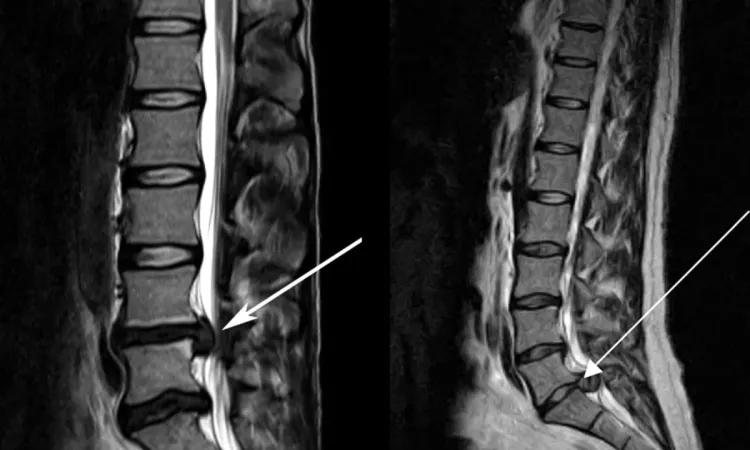

- Грыжа межпозвонкового диска — это уже когда ядро выходит за пределы фиброзного кольца. Вот тут начинается веселье для нервных окончаний: если грыжа задевает корешок — получаем стреляющую, тянущую или иррадиирующую (когда боль отдает в ногу или руку).

- Защемление нерва — это именно контакт грыжи (или отёка, воспалённой мышцы, фасции) с нервным корешком, который и даёт болевой синдром. Но, внимание: сама грыжа болеть не умеет — в межпозвонковом диске нет болевых рецепторов!

Простой пример: грыжа L5-S1 в поясничном отделе может проявляться болью вовсе не в пояснице, а:

- в ягодице,

- по задней поверхности бедра,

- в икре или стопе.

При этом сама поясница может вообще не болеть.

Это объясняется тем, что фасции передают механическое напряжение, а корешки нервов раздражаются в месте компрессии, вызывая так называемые иррадиирующие боли. Такая боль будто «обманывает» мозг, заставляя чувствовать проблему там, где её нет.

Именно поэтому, даже небольшая протрузия в «неудачном месте» может вызывать выраженный болевой синдром, в то время как крупная грыжа в другом сегменте остаётся бессимптомной.